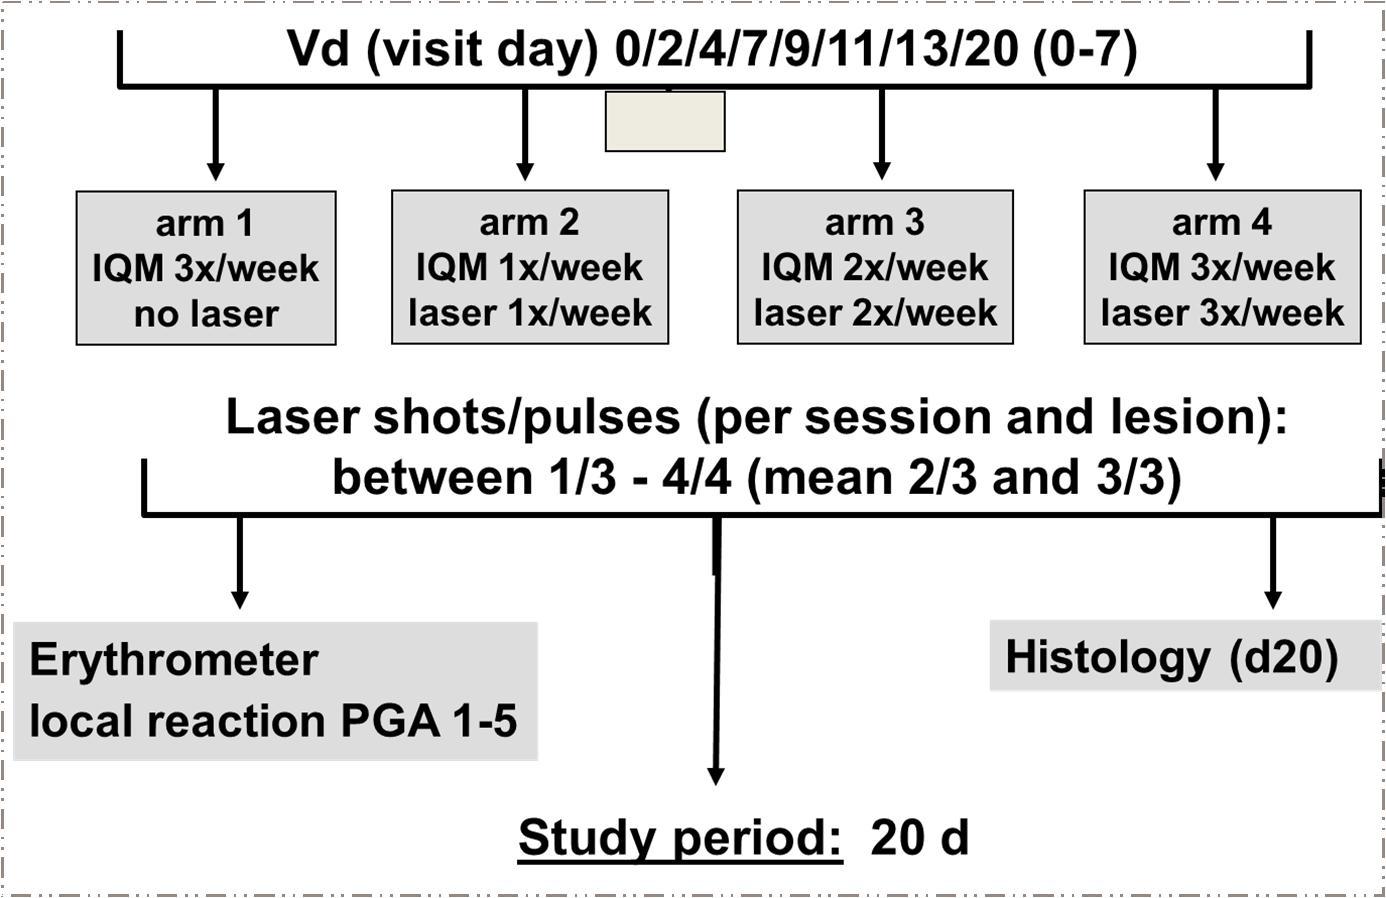

Both studies represent prospective, monocentric, randomised, case controlled, 4-arm, dose finding clinical pilots. Eligible patients were included by a randomisation schedule conducted sequentially, such as the first patient was allocated to the control arm 1, the second to arm 2, the third to arm 3 and so on 19. In the control arm 1 patients were using topical IQM alone as approved by the regulatory authorities (5x /week for BCC patients; 3x /week for AK patients). In the dose finding arms 2 to 4 the frequency of the combined lased and IQM application was 1x/week, 2x/week and 3x/week, respectively (for the BCC study design see Figure 2). Visits were performed at the study days (Vd) 0, 2, 4, 7, 9, 11, 13, and 20. At the last visit a 3 mm punch biopsy was taken and histopathologically analysed to test clearence of the neoplastic lesions. Consequently, the study period counted for 20 days. Those lesions which did not disappear at V20 were further treated with IQM 3x/week for 4 weeks (AK), or 5x/week for additional 3 weeks (BCC, control arm 1). With regard to BCC in arm 2-4, we fully excised the lesions which did not clear.

Skin microporation was performed using the fractionated erbium:YAG laser device. The laser generated pulses are in the mid infrared spectrum (wavelength 3µm) with an 1mJ energy at 250 Hz, which translates to 0.25 W average power. Typically, 300 pores/cm2 per shot were set. AK and BCC lesions were microporated with 1-3 overlapping shots at a pulse rate of 3-10 (Figure 1a and b). Next IQM was applied to the micropores by the investigator.

Figure 1.Dermoscopic pictures of two microporated and imiquimod treated lesions: a) Arm 4 basal cell carcinoma showing an initial erythema at day 2. Microporation was performed with 1 shot at 10 pulses. b) Arm 2 actinic keratosis showing erythema, crusting and erosions at day 11. Microporation was performed with 2 shots at 3 pulses.